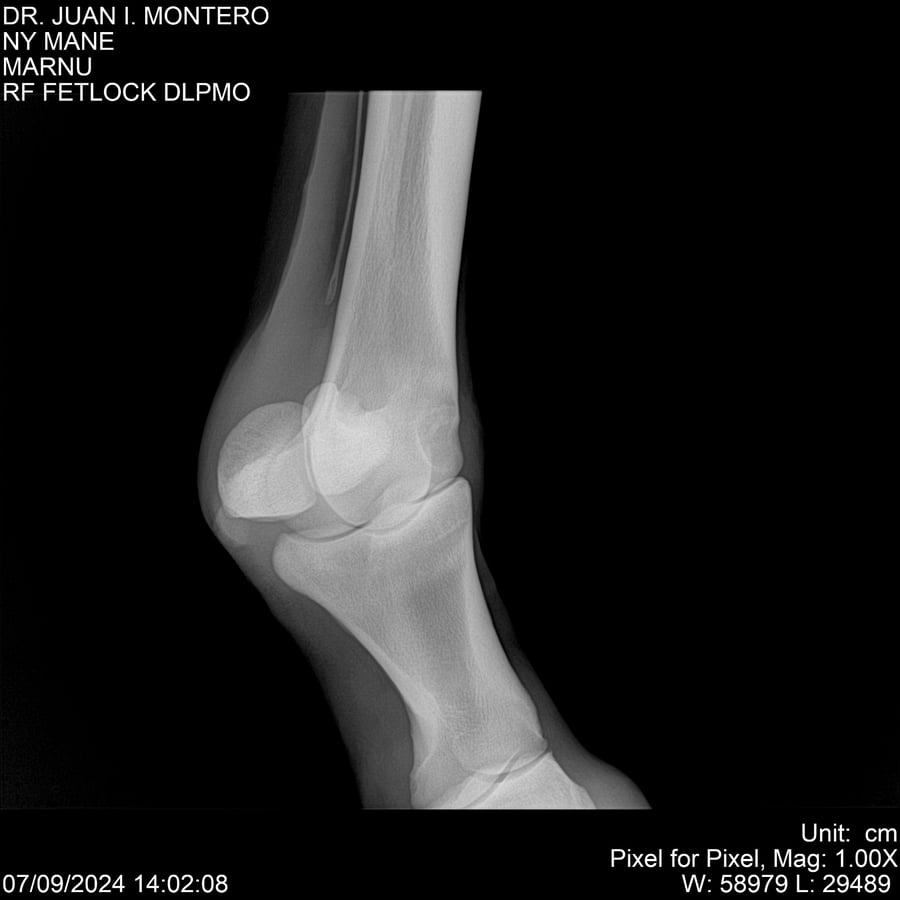

LOTE 20, NY MANE Lote Anterior Volver al remate Lote Siguiente Ficha Contacto Montevideo - Ficha del Lote Identificador: #282520 Categoría: Yeguarizos 76 Visualizaciones ClicData Contacto Empresa: Abelenda N. R., Walter Hugo Nombre*: Teléfono* : E-mail* : Mensaje Enviar Registrese gratis Este contenido Exclusivo está disponible sólo para usuarios registrados Ingresar